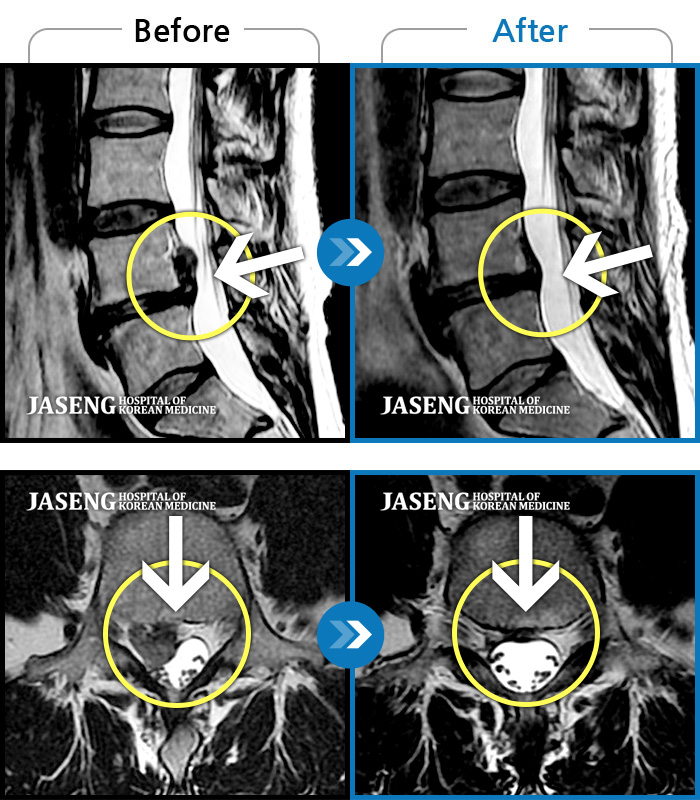

허리디스크

부천 · 최요섭 원장

허리숙이는 일을 한 후 급격하게 발생한 우측하지 방사통, 보행장애, 야간통이 있었다.

촬영시기

2023.07.29 ~ 2023.12.09

2024.01.05

조회수 158